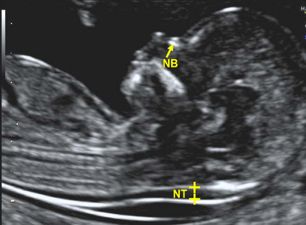

ECOGRAFIA DELLE 12 SETTIMANE O ECOGRAFIA GENETICA

COS'È

Si tratta di una ecografia molto importante che viene eseguita intorno alla 12 settimana di gravidanza. Può essere inserita nell`ambito dell`esame ultrascreening (vedi anche test combinato) o associata al test del DNA placentare.

Cosa valuta?

Già a queste settimane è possibile evidenziare la presenza di malformazioni fetali. Inoltre la misurazione della traslucenza retronucale fornisce informazioni sul rischio di alcune anomalie cromosomiche, patologie malformative e anomalie cardiache.

Nella stessa seduta si valuta la crescita fetale, la posizione della placenta e il liquido amniotico. Si puo` misurare la lunghezza del collo uterino parametro importante per il rischio di parto prematuro